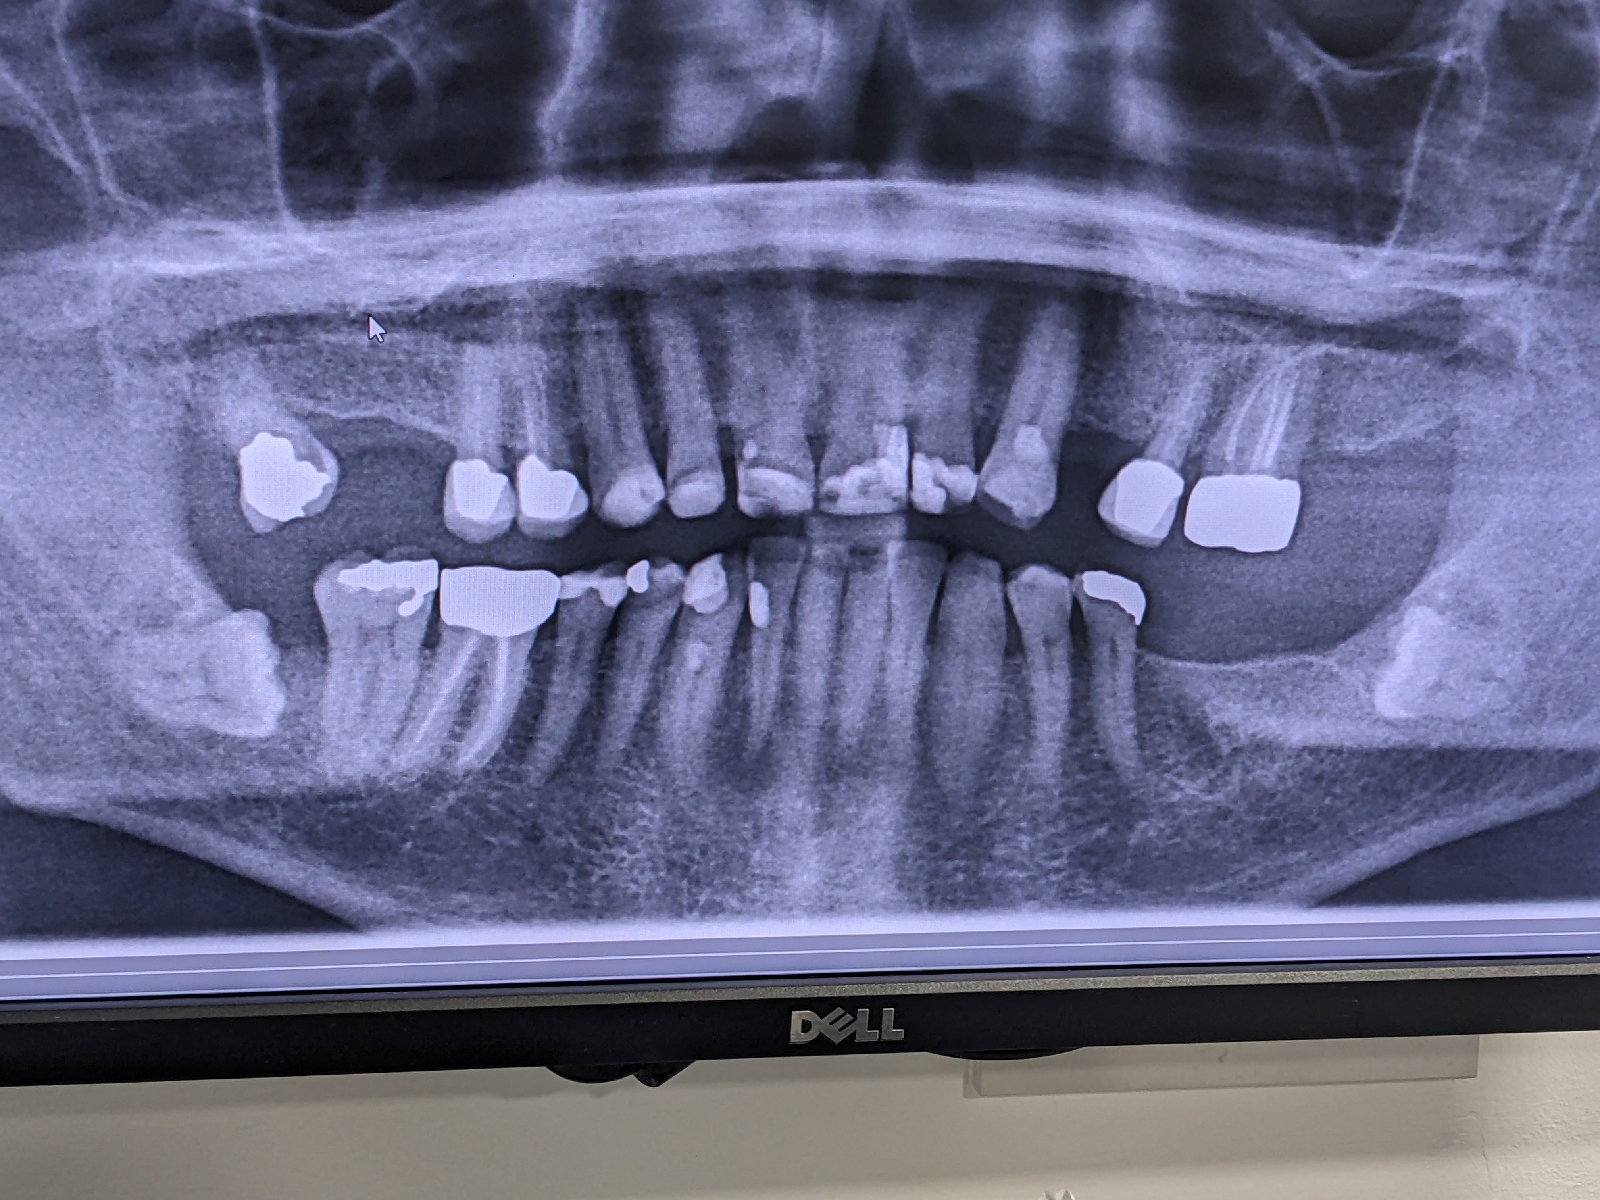

So that was good and then I turned up for my answers at oncology. I laughed that here we were on my Dad's 92nd birthday and the best present I could get him was on its way. Treatable yes, while teeth and tonsils no. They will be in the way of the radiation. So next stop was to be the dentist. My own dentist had been well ahead of the game when she suggested a full X-ray to ensure there was no dental reason for the lump. As the X-ray shows my teeth are shocking and the two sleeping wisdom teeth could well cause problems, wisely thought the dentist at the Western.

I concur and along with the rest of my teeth I said they can all go.

We don't know the pathway the radiation will take as they haven't found the primary. The Pet scan revealed nothing which was good news of a sort.

So I'm off to St Johns to get the tonsils and the teeth out. How many I'll find out when I wake up.